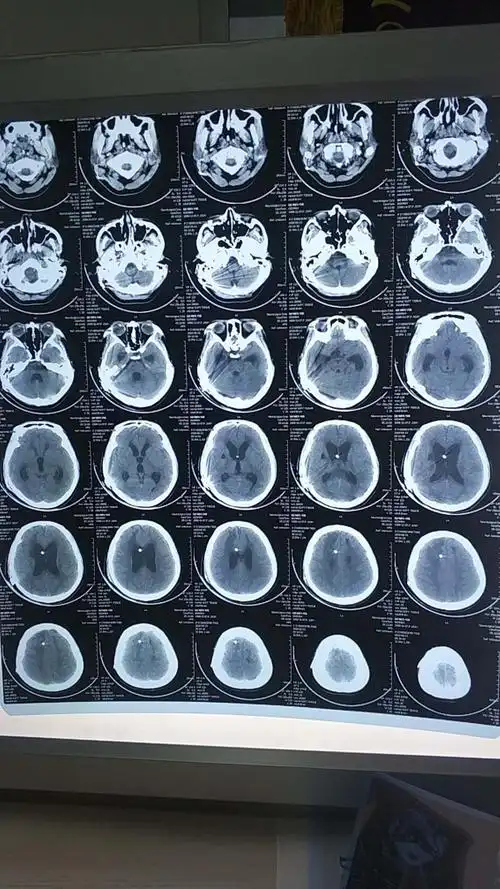

醒36--1重度车祸昏迷,5个月醒啦.